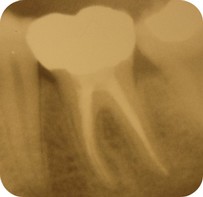

Pri rozsiahlom poškodení korunky zuba zasahujúcim až do dreňovej dutiny alebo pred zhotovením niektorých protetických prác je nutné preliečiť koreňové kanáliky zuba tzv. "vybrať nerv". Ošetrenie koreňových kanálikov sa robí vždy v lokálnom znecitlivení a pomocou najmodernejších nástrojov a techník preparácie. Veľmi často ošetrujeme aj koreňové kanáliky, ktoré už boli raz ošetrené, ale nekvalitne. Zub, ktorý má kvalitne ošetrený koreňový kanálik môže mať rovnakú životnosť, ako zdravý zub.

Tento výkon je tiež nutné vykonať pri liečbe infekcie na hrote koreňa zuba. Koreňové kanáliky je nutné rozšíriť na potrebnú veľkosť, prečistiť a hermeticky uzatvoriť (definitívne endodontické ošetrenie). V niektorých prípadoch nie je možne definitívne ošetrenie koreňových kanálikov pri jednej návšteve, napr. ak je prítomná infekcia na hrote koreňa zuba chronická periodontitída.